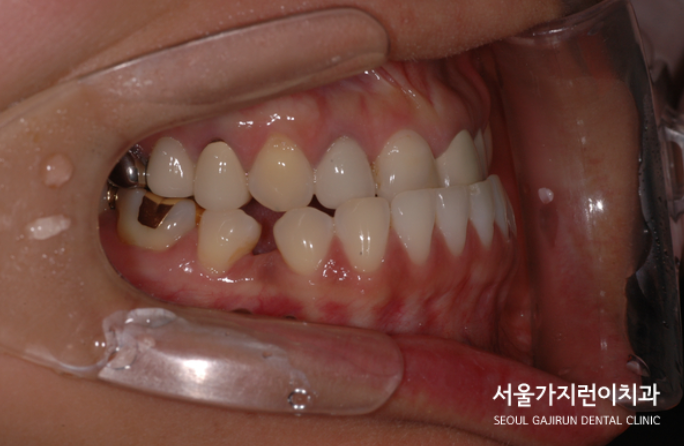

상기 환자분의 경우 심한 전치부 교차교합으로, 흔히 말할 수 있는 주걱턱을 갖고 있었습니다. 교차교갑의 경우 하악의 앞니가 상악 앞니보다 더 앞쪽으로 튀어나와 있는 경우를 말하는데요. 교차 교합이 있는 경우에는 아래턱이 더 많이 나온 것같은 모습이 연출됩니다. 특히 이런 경우는 가족력이 있는 환자분들에게 발생할 수 있는데요. 치아는 심미적으로 큰 부분을 차지하기 때문에 교차교합이 있는 경우라면 외모적 자신감이 하락할 수 있습니다. 아주 심각하다면 치아가 맞물리지 않아 저작기능에도 문제가 될 수 있겠죠. 특히 해당 환자분의 경우 보철치료를 마친 케이스기때문에 다수의 보철물을 확인할 수 있었는데요. 만약 비수술 교정으로 하악 치열을 후방으로 이동하게 되었다면 브릿지를 포함한 다수의 보철물때문에 정밀한 교합달성이 어려운 것으로 진단되었습니다.

그래서 환자분의 경우에는 설측교정으로 치아교정을 진행하길 원했고 두 개의 와이어를 걸 수 있는 탄댐설측교정 방식을 통해 치료를 진행하게 됐습니다. 하악 정치를 함입 시킴과 동시에 미니스크류를 이용해 하악을 후방으로 이동시켰는데요. 치료는 매우 안정적으로 진행이 되었으며 브릿지를 포함한 다수의 보철물도 안전하게 좋은 교합이 달성되었습니다.